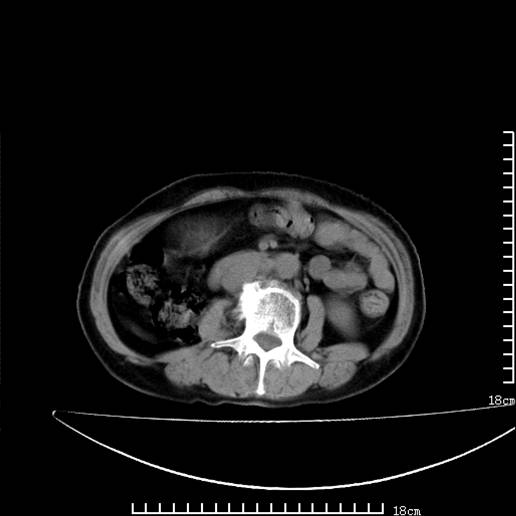

以下是引用pujunzhi在2008-5-30 15:31:00的发言:[br]异位肾—盆腔肾。当看到肾窝无肾脏时,要想到孤立肾和异位肾,异位肾最常见是盆腔肾,偶见胸腔,易误认为肺占位,只要想到就不会漏诊。建议增强扫描。